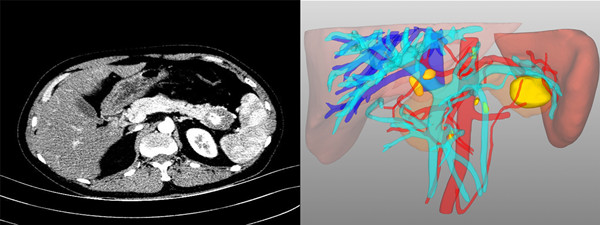

患者2,男,44岁,诊断“原发性肝癌”。术前评估:全身评估及营养评估未见异常;肝功能Child-Pugh-Turcotte分级A级,ICGR15 0.6%;病灶及可切除性评估:肿瘤位于肝脏V-VIII段,约8*7.5*7.5cm大小,侵犯肝右静脉中远端及相应肝段Glisson系统;门静脉无变异(A型),右肝动脉发自肠系膜上动脉,裂静脉与肝中静脉根部共干;肝内胆管无扩张;拟行解剖性右半肝切除术,患者总肝体积1877.27ml,标准肝体积1191.08mL,右半肝体积1126.23mL,左半肝体积为751.04,Rsr为63.1%,结合当前患者肝功能及ICGR15水平,Rse为40% 患者3,男,36岁,诉“发现胰体尾占位1周”,术前诊断“胰体尾实性假乳头状瘤”。患者因颈椎病,在骨科住院查出胰腺占位性病变,转入我科治疗,术前评估:全身评估及营养评估未见异常;肝肾功正常:肿瘤位于胰尾部近脾门处,经三维重建后,可见脾动脉及脾静脉分两支型,紧紧包绕肿块,决定腹腔镜下行胰体尾联合脾脏切除。术中探查见上脾门区致密粘连,给手术来带了一定的困难和挑战。凭借术中三维精准导航和精细的手术解剖,胰体尾及脾脏被顺利切除。手术历时2.0h,术中出血约50mL,目前患者恢复良好,拟于近日出院。 术后在谈及专业划分后一周的肝胆胰外科工作时,陆宏伟教授表示,肝胆胰外科手术操作犹如荒野探险,术前永远无法完全把握未知的前方有哪些解剖变异和挑战等待着你,因此只能通过术前精准的治疗规划、术中结合影像学进行精细的外科操作和术后精心的个体化管理,使患者最大程度的获益。 陆宏伟教授师从于我国著名肝胆胰外科专家董家鸿院士,对于肝胆胰良恶性肿瘤和胆管扩张症的精准诊疗及肝脏移植术具有丰富经验。目前陆宏伟教授团队已与北京清华长庚医院董家鸿院士团队、中国人民解放军总医院段伟东教授团队建立长期临床及科研合作关系,这将进一步提升团队的肝胆胰疾病诊断和外科治疗水平。